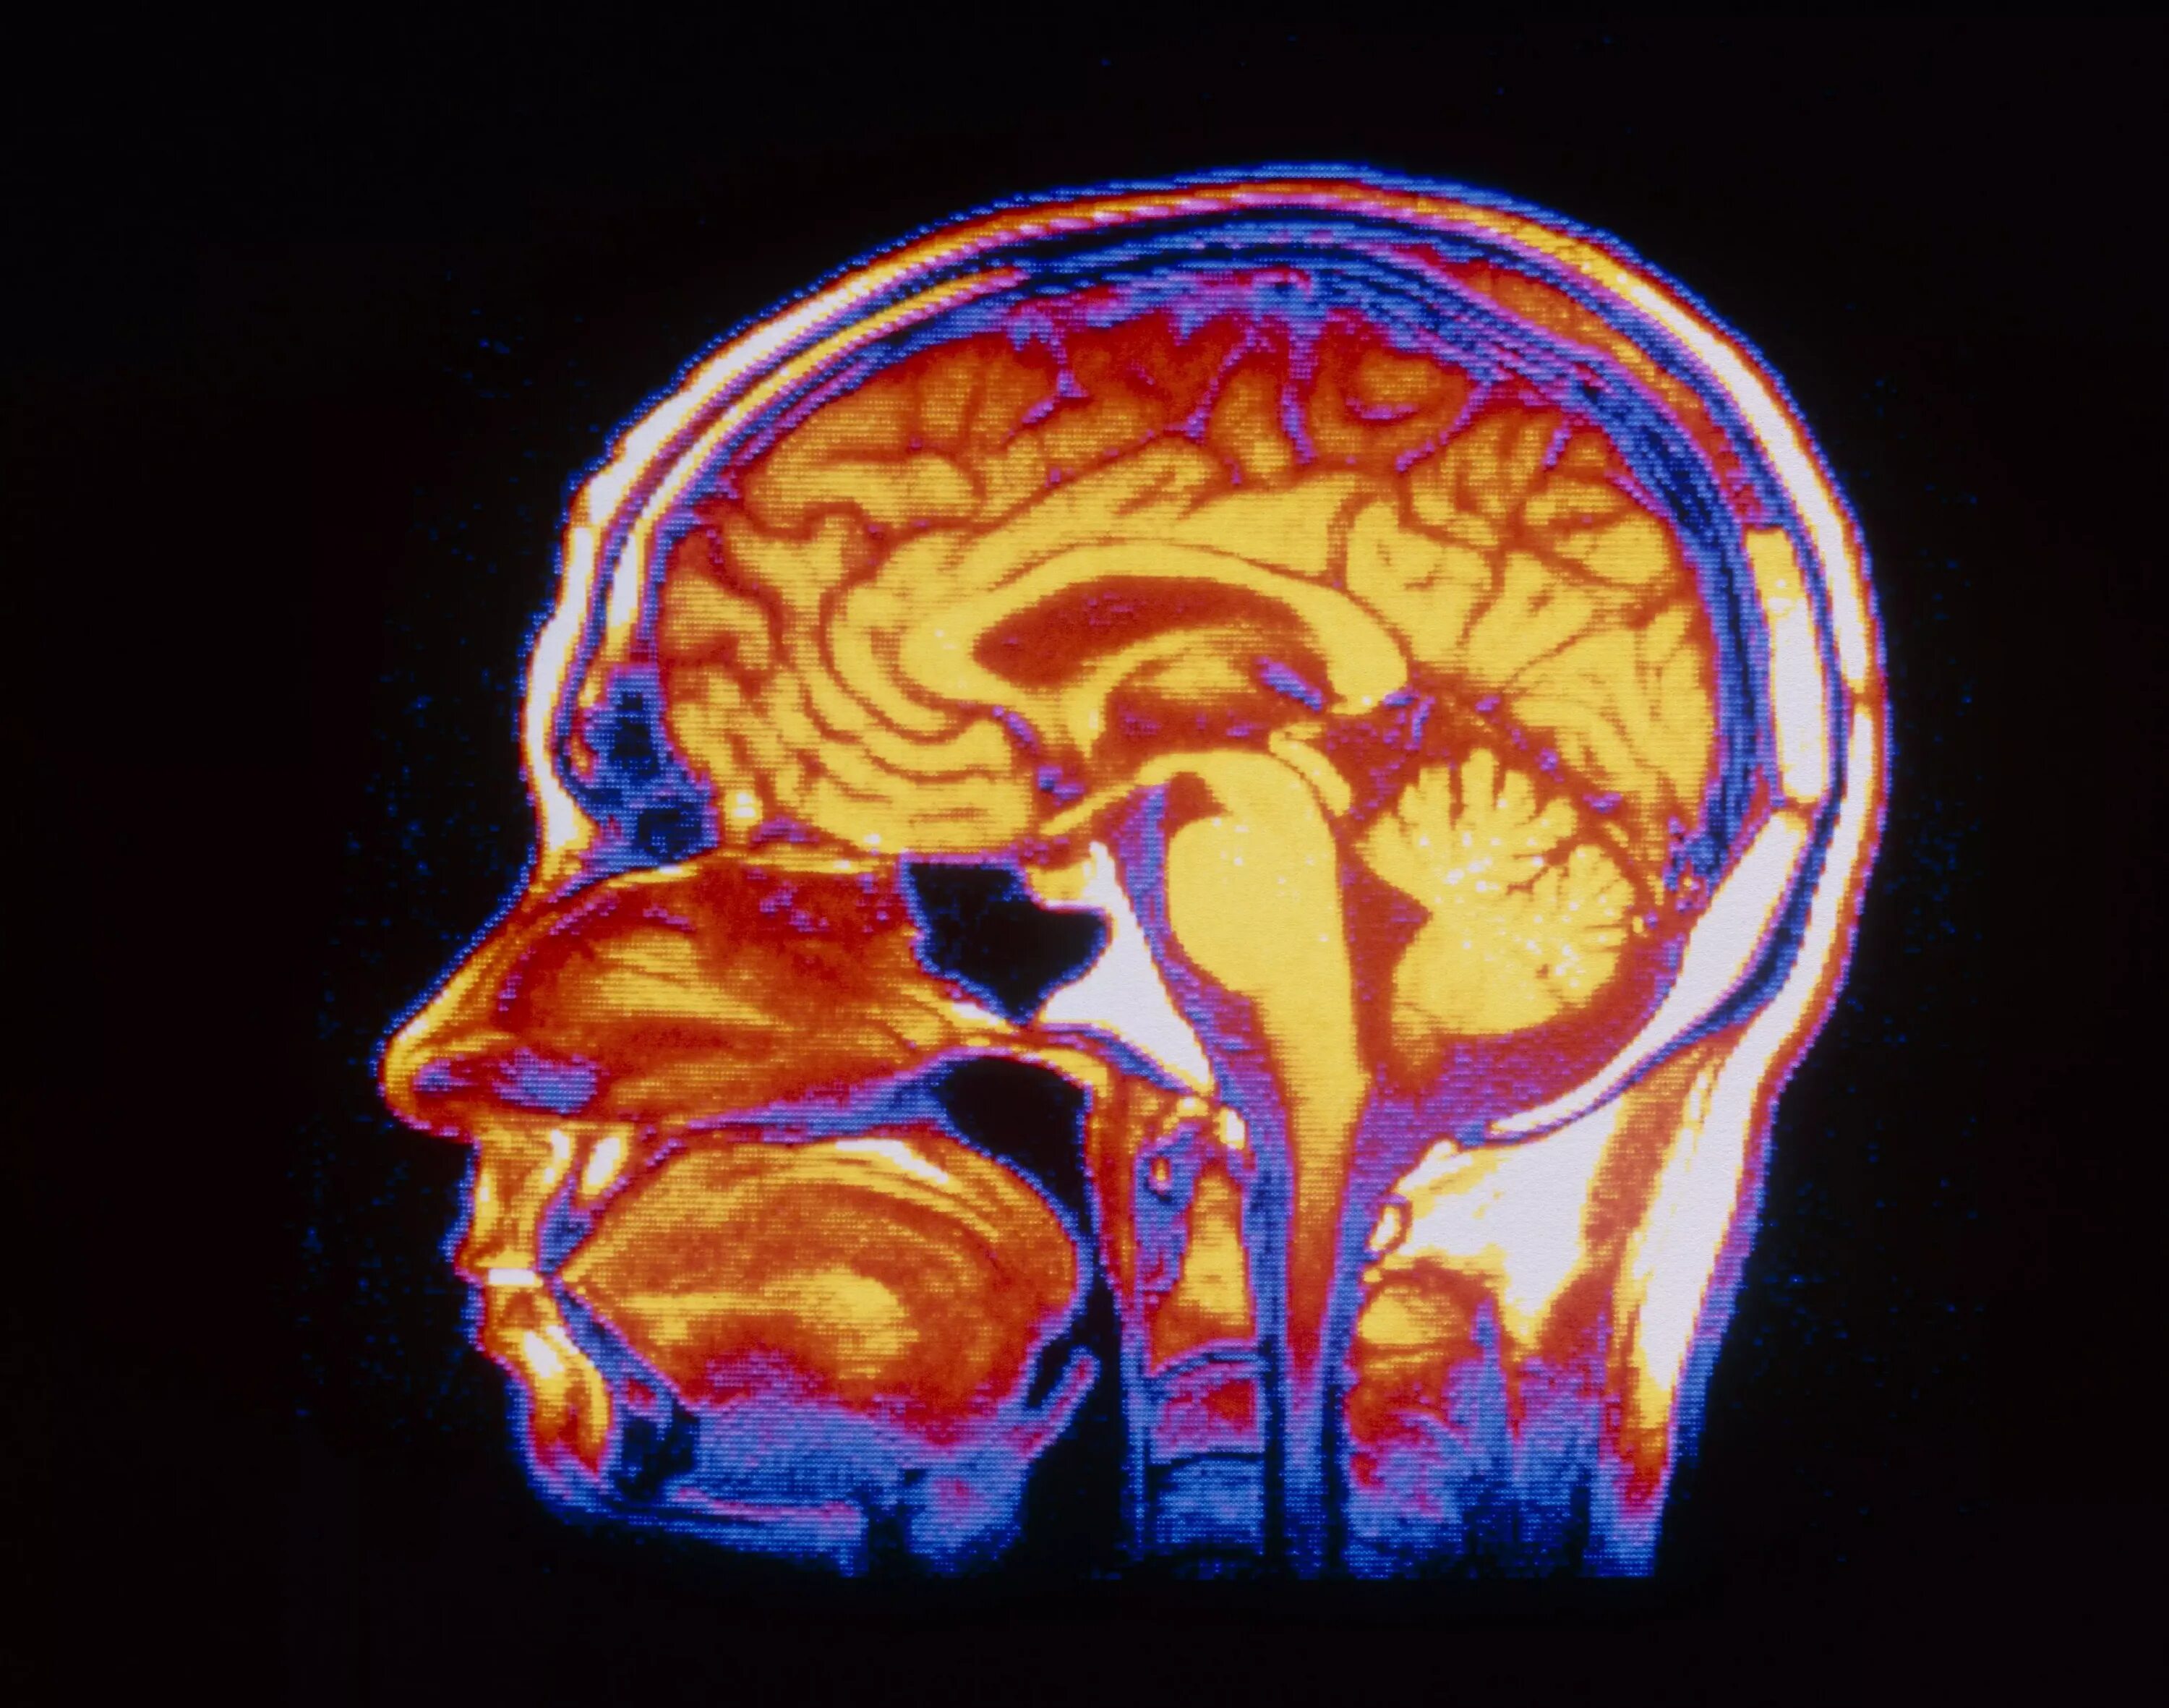

Давление изнутри головы